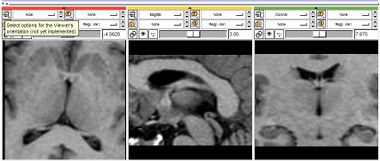

*Initial Label Image: The output of the [[Slicer3:Module:Bubble_Maker-Documentation|Bubble Maker]] module.

*Feature Image: The output of the [[Slicer3:Module:Target_Preprocessing-Documentation|Target Preprocessing]] module.

*Propagation Weight: Relates to the amount of inflating force applied inside the surface (can be negative).

*Curvature Weight: Influences roundness of the resulting interface. Greater weight, greater roundness. Prevents leaking through narrow openings.

*Advection Weight: It weights the influence of the advection term, which behaves like a magnet attracting the interface towards edges.

*Number of Iterations: Indicates duration of the evolution.

*Output Label Image: Resulting segmentation.

The parameters have the following meaning:

• Propagation Weight: Relates to the amount of inflating force applied inside the surface (can be negative).

• Curvature Weight: Influences roundness of the resulting interface. Greater weight, greater roundness. Prevents leaking through narrow openings.

• Advection Weight: It weights the influence of the advection term, which behaves like a magnet attracting the interface towards edges.

• Number of Iterations: Indicates duration of the evolution.

• Output Label Image: Resulting segmentation.